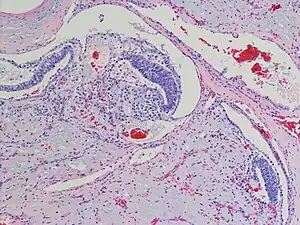

| Polyembryoma of the ovary, H&E stain | |

Why it occurs is not well understood.[1] Polyembryoma has features of both yolk sac tumour and undifferentiated teratoma/embryonal carcinoma, with a characteristic finding of embryoid bodies lying in a loose mesenchymal stroma.